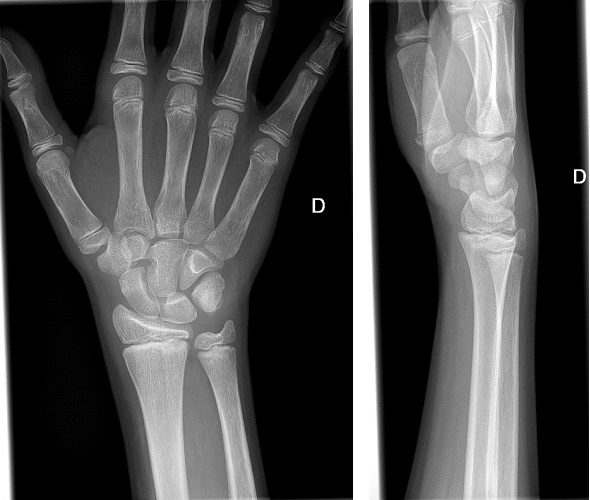

A los 3 meses, consulta de nuevo por inflamación en muñeca derecha, sin antecedente traumático, acompañado de astenia de 3 días de evolución. Se realiza radiografía de muñeca, en la que se evidencia irregularidad en la epífisis cubital (informada como imagen dudosa de fractura), solo visualizada en proyección anteroposterior (Fig. 1). Es valorado por Traumatología, donde se descarta posible origen traumatológico, y es dado de alta con AINE.

| Figura 1. Radiografía de muñeca derecha 2.º episodio de artritis. Irregularidad en la epífisis cubital (informada como imagen dudosa de fractura), solo visualizada en proyección anteroposterior |